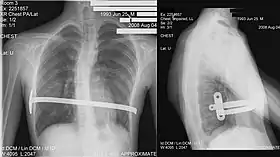

Bar removal

After a period of two to four years,[3]:343 the surgical stainless steel bar is removed from the patient's chest. This procedure lasts approximately ninety minutes. The length of time that the patient stays at the hospital following the bar removal procedure varies, depending on the amount of new bone growth surrounding the bar. Accordingly, the length of time may range from a few hours to several days, or up to one week.